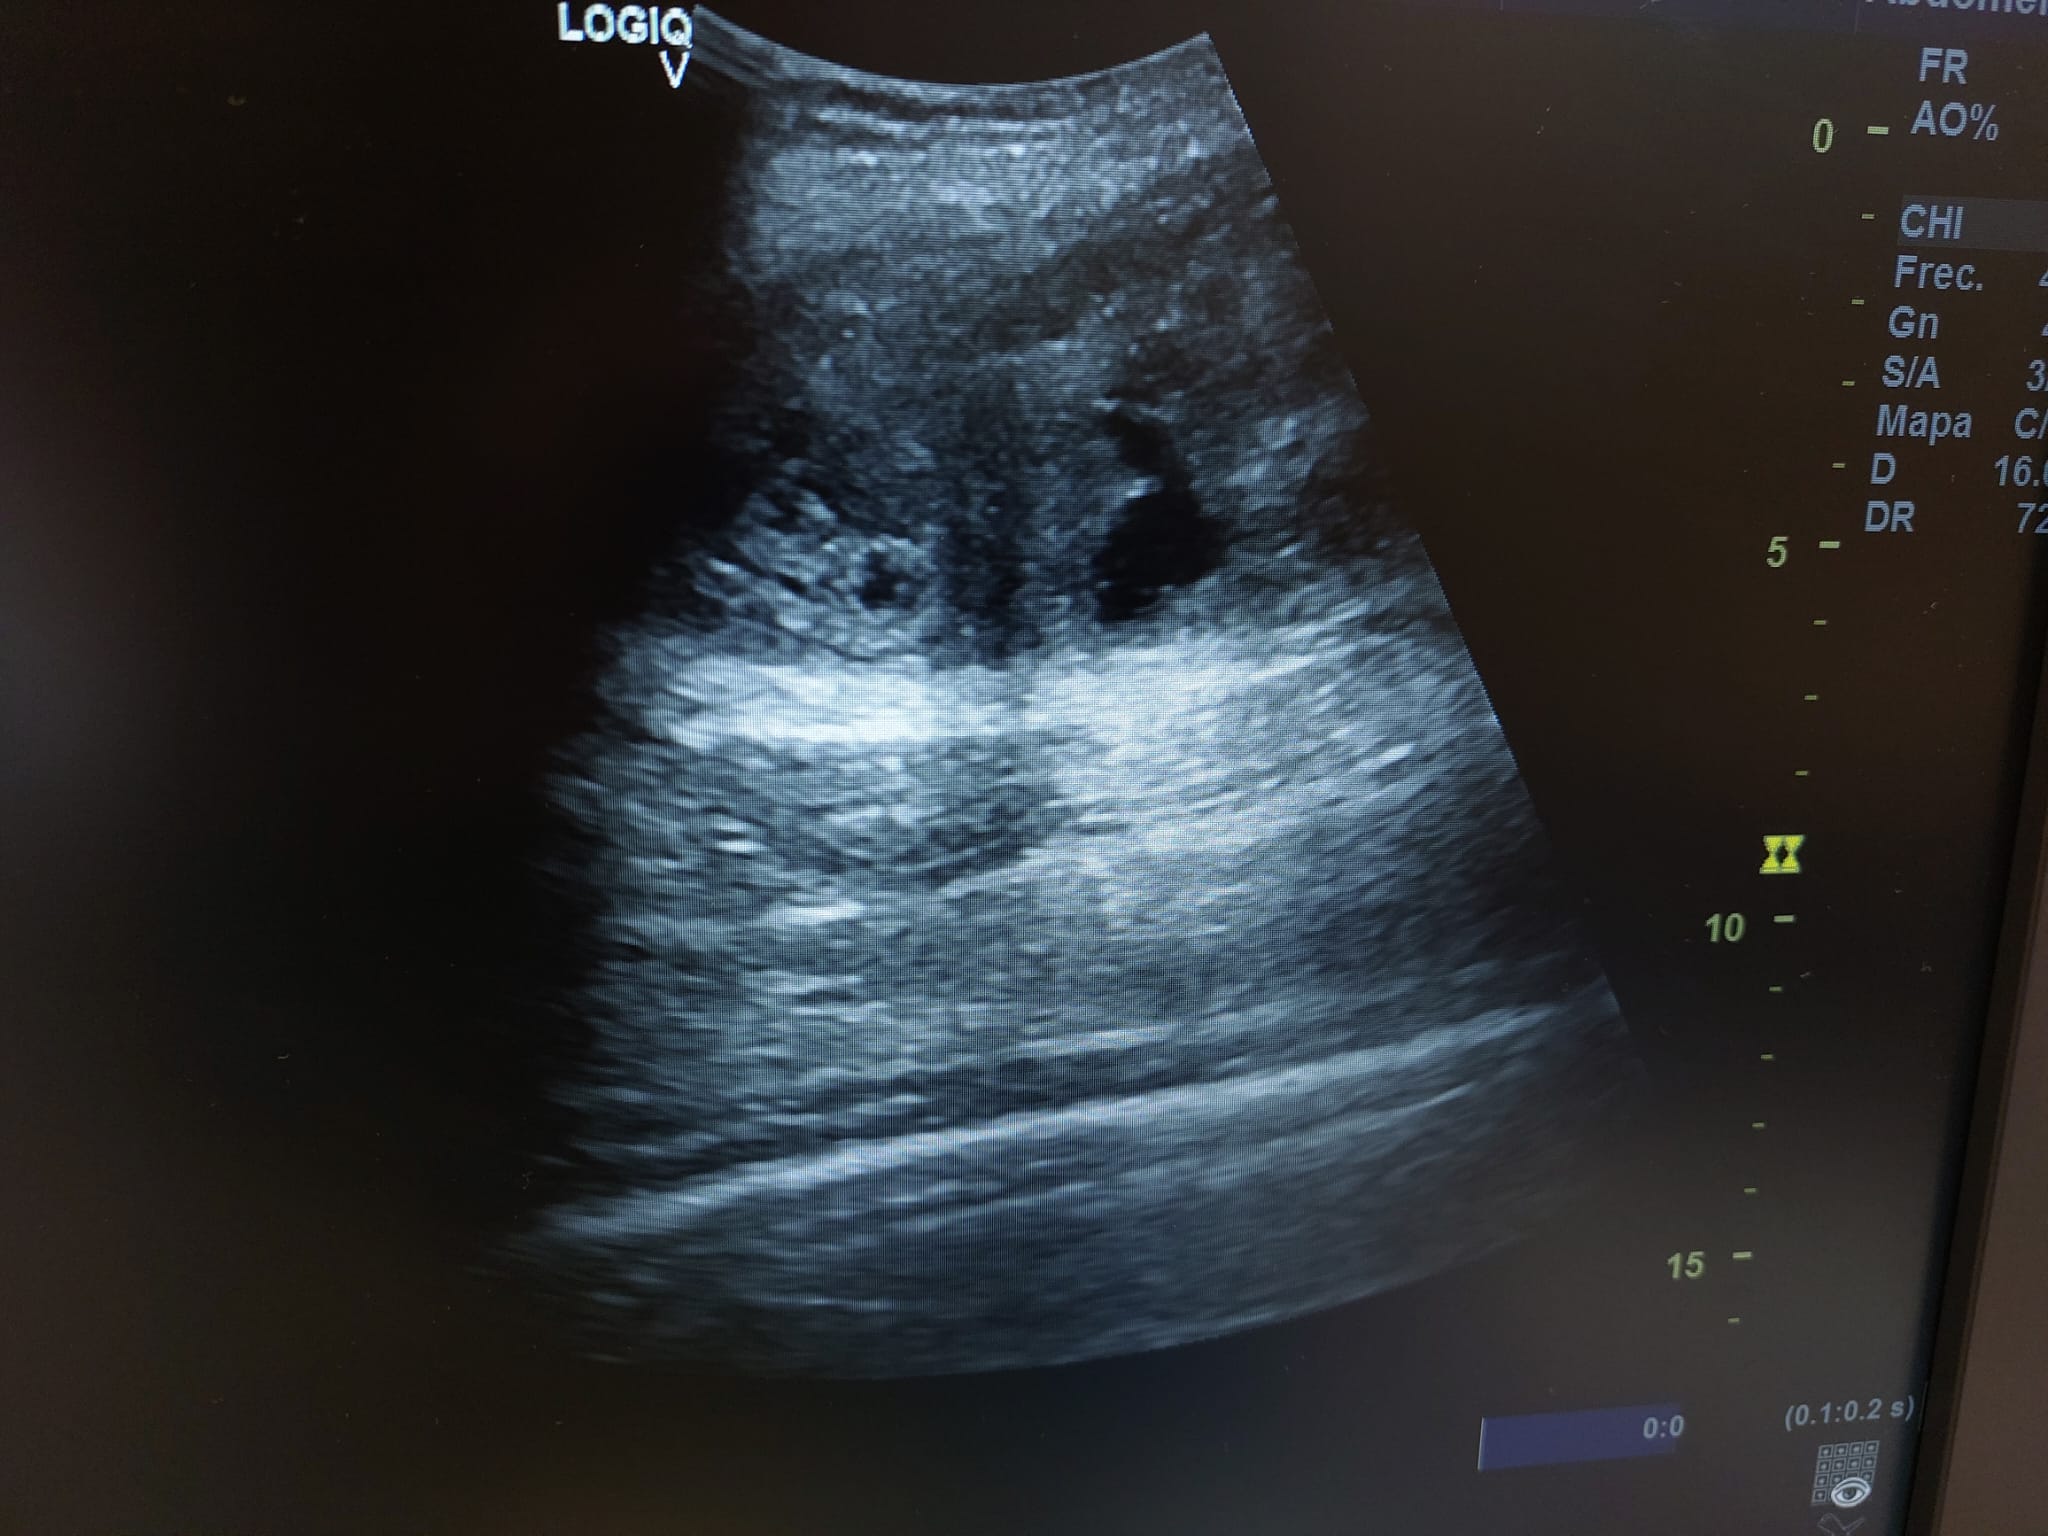

Descripción de los hallazgos ecográficos y las imágenes más relevantes para la resolución del caso

Se realiza ecografía observando colección anecoica a nivel muscular compatible con hematoma organizado, de aproximadamente 7 x 4 cm.

En el seguimiento se observa evolución tórpida sin mejoría clínica y en la ecografía de control se observa aumento notable de tamaño respecto al previo, estructura heterogénea de imagen anecoica con septos internos. Se aprecia edema intramuscular perilesional y captación al activar el Doppler. Se plantea la posibilidad de un hematoma sobreinfectado o, debido a su importante crecimiento, una probable etiología neoplásica. Tras hallazgos descritos en consulta, COT solicita de forma urgente la realización de RNM y biopsia de la lesión. Posteriormente, el resultado de las pruebas complementarias confirman diagnóstico de sarcoma histiocítico.